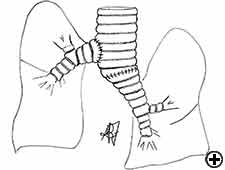

Carinal resection is a complex and aggressive procedure for the treatment of bronchial tumors involving the carina, the tracheo-bronchial angle or the distal portion of the trachea (Figure 1). The airway is reconstructed by anastomosis of the opposite main bronchus (tracheal sleeve pneumonectomy) or both bronchi (isolated carinal resection) to the lower trachea (Figure 2). The most common indication for a sleeve pneumonectomy is a tumor involving the origin of right main bronchus or extending into the lower trachea. Left sleeve pneumonectomy is rarely indicated since the left main bronchus is considerably longer than the right one and, in the case of carinal infiltration, tumor usually invades the structures in the subaortic space as well, which frequently implies inoperability. An isolated carinal resection and reconstruction may be applicable for centrally located, low grade and small tumors of the carina not extending so far to the main bronchi. Carinal resection represents a challenge for thoracic surgeons and anesthesiologists related to demanding intraoperative airway management, the technique of anatomic reconstruction and the risk of significant postoperative morbidity, mortality and poor long-term outcome [11].

In isolated carinal resection and reconstruction, applicable for centrally located, low grade and small tumors (Video 8), the right and left main bronchi can be medially sutured to create a new carina, that is subsequently anastomosed to the distal trachea (Figure 2C and Video 9). A less common technique provides the resection of the carina followed by an end-to-end anastomosis between the left main bronchus and the trachea, followed by anastomosis of the right main bronchus to the lateral, cartilaginous wall of the trachea, paying attention to stay at least 2 cm above the first anastomosis (Figure 6). When more advanced tracheal involvement is present, two alternative techniques may be used to avoid excessive tension: an end-to-end anastomosis between the right main bronchus and the trachea, followed by anastomosis of the left main bronchus to the lateral, cartilaginous wall of the bronchus intermedius or an end-to-end anastomosis between the left main bronchus and the trachea, followed by anastomosis of the right main bronchus to the lateral, cartilaginous wall of the left main bronchus (Figure 7). In all of cases a wide hilar release is mandatory to reduce tension on the anastomoses.